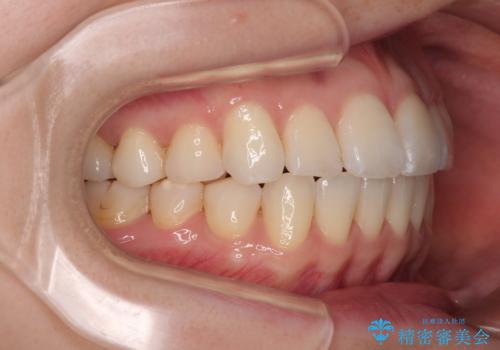

前歯のデコボコと口元の膨らみを治したい ワイヤー装置での非抜歯矯正

舌のトレーニングは不十分でしたが、1年半ほどで治療を終えることができました。

舌の突出癖が残っていると、容易に後戻りしてしまうため、トレーニングは継続するように指導しています。